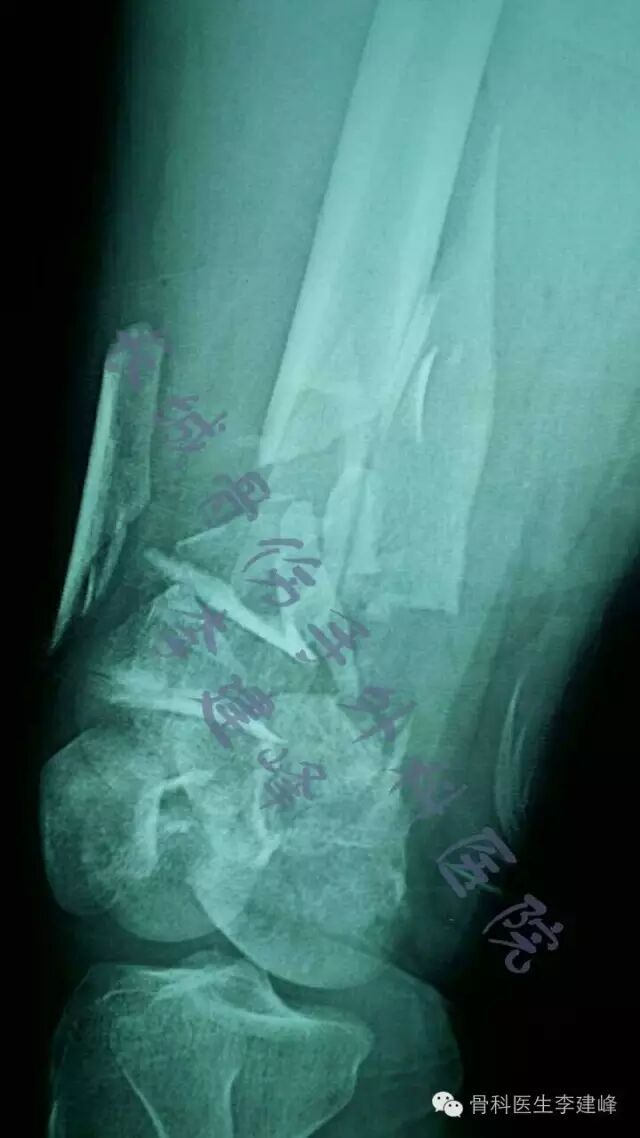

Two case:

术前